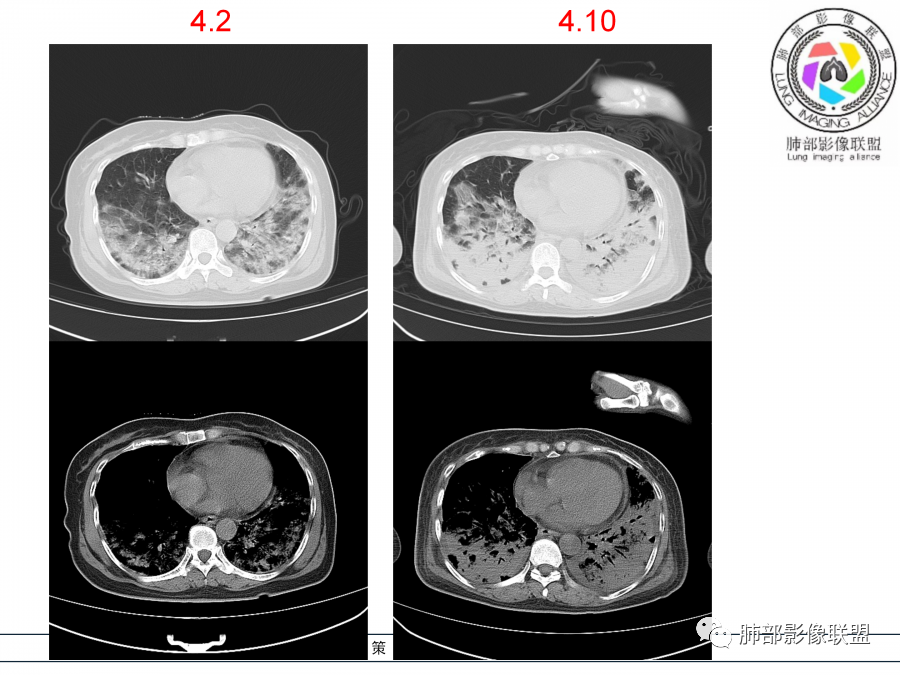

影像,第一次双肺中下叶胸膜下多发斑片状实变影,部分融合成,周围散发磨玻璃影,磨玻璃影内可见小叶间隔及小叶内间隔增厚,病变平行于胸膜,第二次间隔8天,双肺实变影明显进展,有重力作用,支气管近端堵塞,进展较快,临床有发热,血沉高,狼疮SLE阳性,考虑1:OP(机化性肺炎)2:SLE相关肺炎,建议支气管镜灌洗液病原学检测。

➢患者7天前起因受凉后出现阵发性咳嗽,无明显时间规律性,咳黄白粘痰,发热,体温最高达39.5℃,伴鼻塞、流清涕,。两肺下叶背段,后基底段为主的渗出性的病变,短时间内病变明显的增多,双侧胸腔积液,狼疮全套抗R0/SS检测阳性,考虑狼疮性肺损,机化性肺炎?鉴别结核

老年女性,咳嗽咳痰伴发热7天,白细胞不高,血沉快,降钙素原不高。其他化验未见明显异常,狼疮全套抗Ro/SSA阳性,双肺野靠近胸膜下磨玻璃实变影,支气管通畅,有充气征,沿胸膜下分布,有细网格征,7天后进展明显,实变影加重,胸膜肥厚,胸水不明显,心包少量积液?抗感染治疗无效,考虑非感染性疾病可能性大,结缔组织相关性肺病?狼疮性肺炎?机化性肺炎?鉴别病毒性肺炎。

老年女性,咳嗽咳痰发热7天。无气促。白细胞计数不高,PCT稍高,PPD(+),抗Ro/SSA阳性。CT:双肺野靠近胸膜下磨玻璃实变影,支气管通畅,有充气征,沿胸膜下分布,有细网格征。予抗生素治疗,8天后复查胸部CT见病灶范围扩大,实变影加重,胸膜肥厚,胸水不明显。抗感染治疗无效,考虑有:1.非感染性疾病:结缔组织相关性肺病,支持点:肺部CT表现为间质性炎症病变,抗RO/SSA(52)阳性;2.病毒性肺炎:患者无气促症状,可能性小;3.肺结核。

两肺胸膜下磨玻璃影➕实变影,非叶段分布,基底部明显,抗感染治疗无效,迅速进展伴胸腔积液。无明显低氧血症。

第一次双肺中下叶胸膜下多发斑片状磨玻璃及实变影,病变平行于胸膜,支气管通畅,8天后,双肺实变影明显进展范围扩大,部分支气管近端堵塞,进展较快,胸腔积液,抗感染治疗无效,考虑:非感染性疾病:结缔组织相关性肺病。鉴别机化性肺炎。